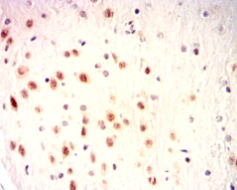

IHC    1/100 - 1/500